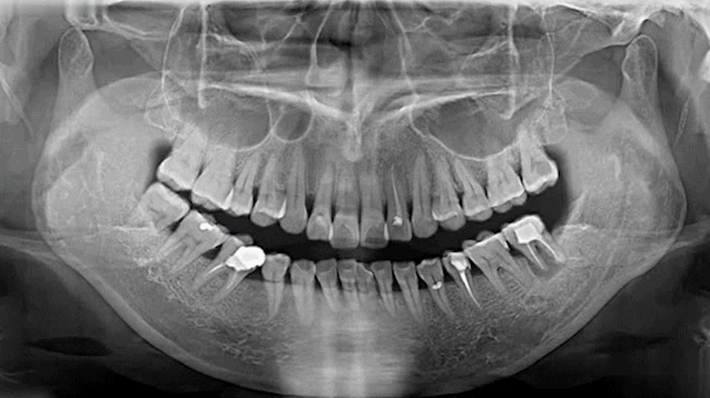

竟然用牙齿开瓶盖!牙齿不要了吗?……